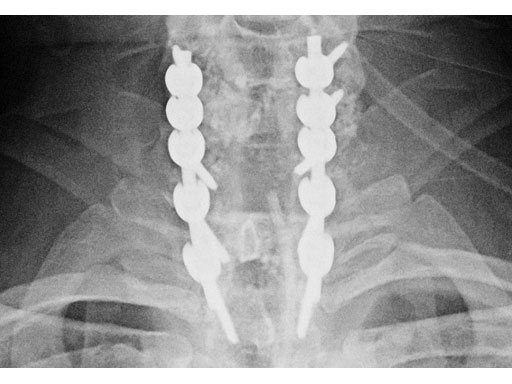

A 28-year-old, 109 kg man was involved in a high-speed motor vehicle collision with C7-T1 jumped facet and T1 teardrop fracture. The patient had ASIA E with motor score of 100. He had failed closed reduction in the emergency room then was taken to OR emergently for open reduction and C5-T2 posterior segmental instrumentation with synapse 4.0. The patient did well postoperatively with no evidence of collapse or failure.

Synapse 4.0 was the ideal solution to treat this injury. This was a heavy patient with a highly unstable injury at the cervicothoracic junction. Synapse 4.0 enabled stabilization of his injury with a rigid construct. It has all the benefits of the 3.5 system but is more rigid and allowed use of one system as opposed to using the 3.5 system and a 6.0 rod system with the nuances of a tapered rod. The author was able to place C5 and C6 lateral mass screws utilizing the Magerl technique and C7, T1, and T2 pedicle screws.